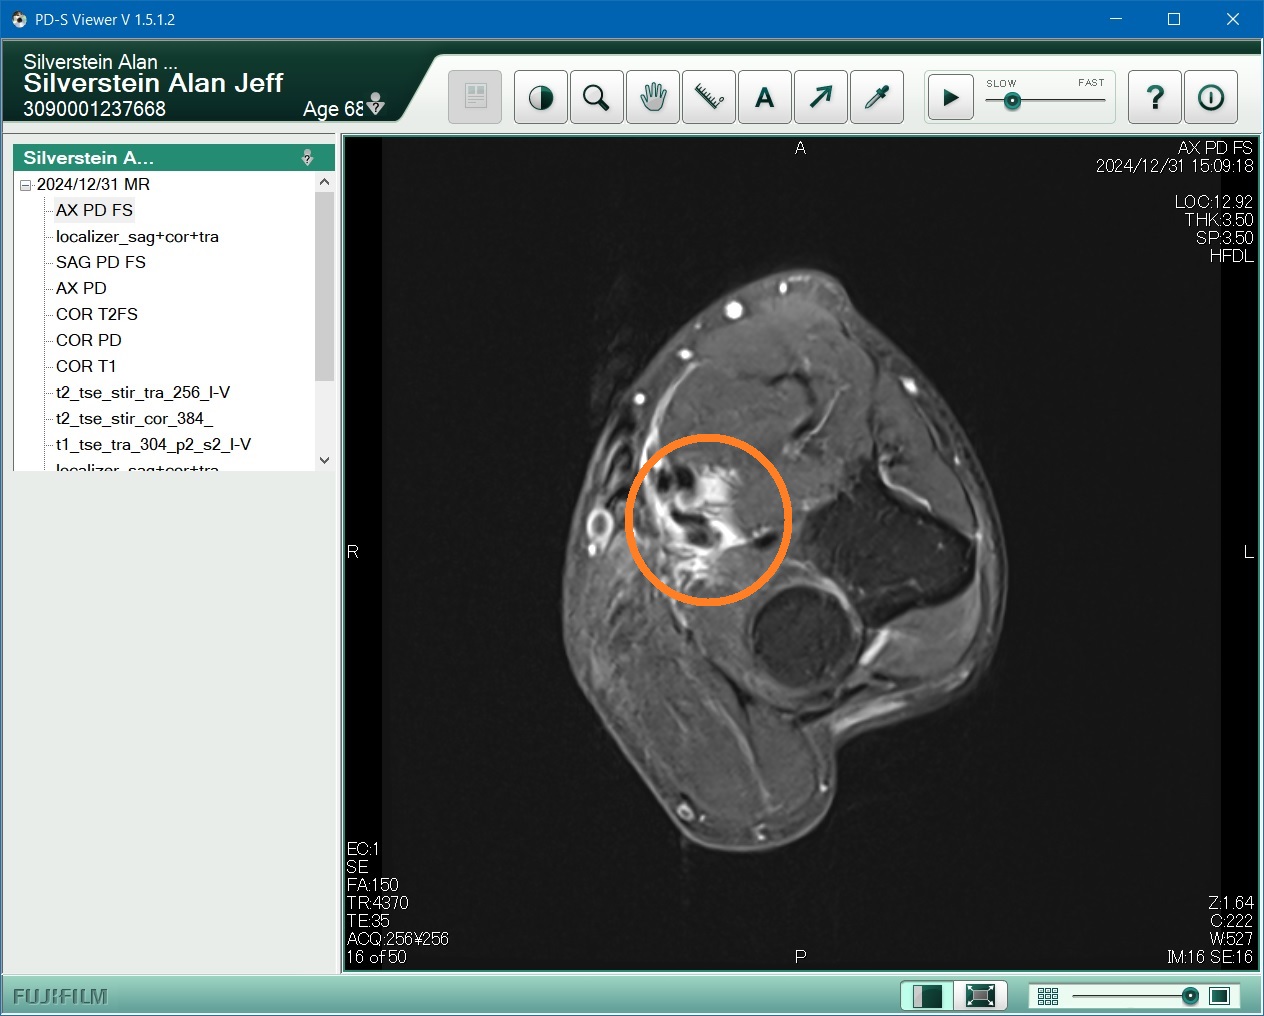

Here are just two "axial" MRI slices out of a a variety of groups, each with a dozen or more images.

12/31 MRI axial picture 1

The first MRI image is looking outward beyond my elbow. The black areas are tendons or arteries, not supposed to be so messy. The white is fluid (edema).